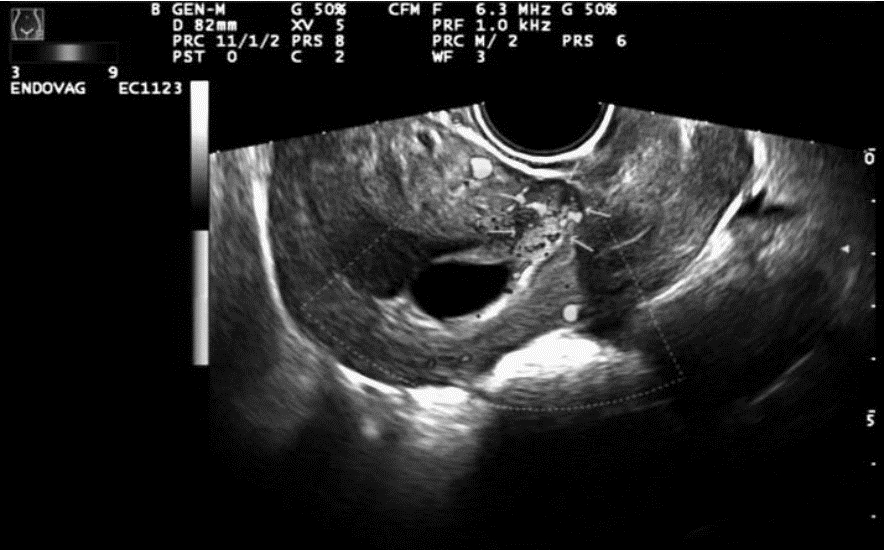

2 结果CDFI正确诊断切口妊娠和下段妊娠分别为17例、14例(图 1、图 2),CEUS正确诊断切口妊娠和下段妊娠分别为19例、20例(图 3、图 4)。CDFI、CEUS、CDFI及CEUS联合在切口妊娠与宫腔下段妊娠的鉴别诊断中差异具有统计学意义(P<0.05)。见表 1。

![]() |

| 图 1 孕囊位于子宫前壁峡部,CDFI显示前壁峡部与孕囊之间血流信号 |